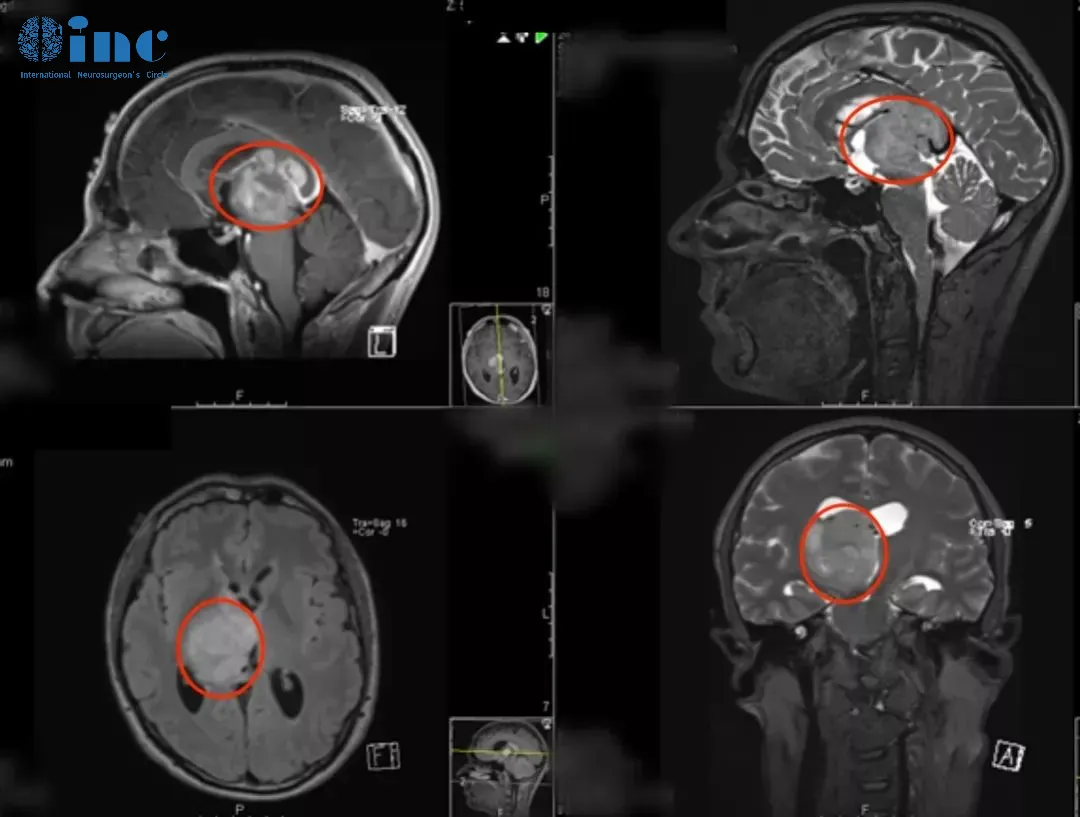

26岁足球运动员巨大丘脑占位次全切后10天出院

患者情况:在一次头部轻伤后近3个月来逐渐出现复视、肢体活动欠灵活、容易急躁,遂当地医院就诊。发现巨大丘脑占位并压迫脑干,当地医院表示,目前虽无明显肢体瘫痪症状,但是手术难度风险极大,有昏迷、失明、术后瘫痪、感觉障碍等可能,且肿瘤切除率有限。后慕名求诊于德国巴特朗菲教授。

诊断:右侧丘脑胶质母细胞瘤(胶质瘤4级),压迫右侧中脑WHO 4级,MGMT甲基化。

主刀医生:INC巴特朗菲教授

治疗后情况:在术中电生理监测(SEP和MEP)下,巴特朗菲教授采用右侧额叶旁开颅术和通过额叶纵裂经胼胝体入路,肿瘤得到次全切除。手术顺利,无围手术期并发症。术后当天拔除气管,无神经功能缺损。术后第2天转到普通病房。术后左手有轻微精细运动欠灵活,术后1周左右明显改善。术后10天出院,保持清醒,精神可,没有颅神经缺损;没有视野缺陷,肢体感觉和运动正常。

术后MR显示肿瘤次全切除,占位效应明显解除